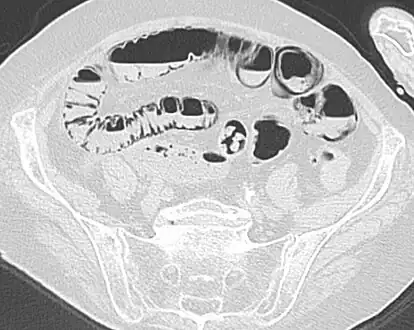

Pneumatosis intestinalis at computed tomography in intestinal ischemia. Lung window for better representation of the gas deposits in the intestinal walls. Coronal reconstruction.

Pneumatosis intestinalis in computed tomography with intestinal ischemia. Lung window for better representation of the gas deposits in the intestinal walls.